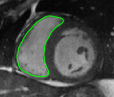

![]() |

| image + boundary | global optical flow | our method | our method (motion decomp.) |